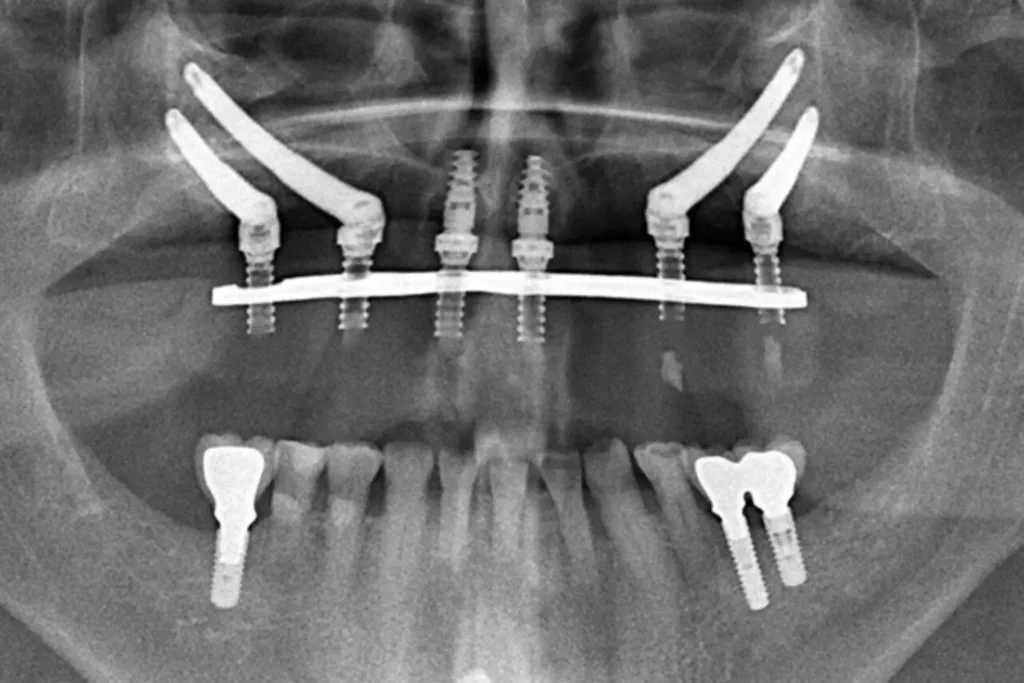

Zygomatic, also known as ‘Zygoma’, are longer than standard dental implants that instead of relying on jawbone, transverse the poor area of your upper jaw to anchor into the underside of the cheekbones from the inside through the sinus space.

This approach is used for severely resorbed upper jaws and is designed to facilitate immediate rehabilitation with fixed replacement teeth.

The zygoma implants are inserted in the back section from within the mouth, along with one or more additional regular implants in the front part of your jaw, or in the most sever of cases two zygomatic implants may be placed on each side, which is referred to as Quad Zygoma .